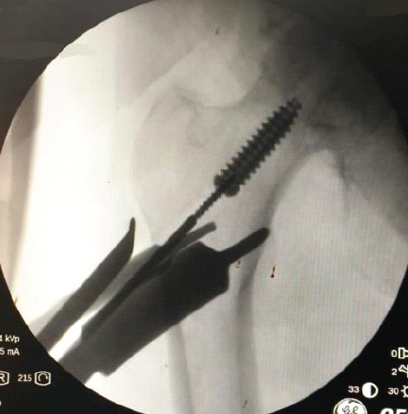

Aneurysmal Bone Cyst Presenting as a Pathological Subtrochanteric Femur Fracture in an Adolescent: A Case Report

Chandrashekhar R Rai , Sandeep V Gavhale , Vijaysing Chandele , Alok P Yadav , Chinmay S Torne , Vishal B Karpe

………………………………p.89-93